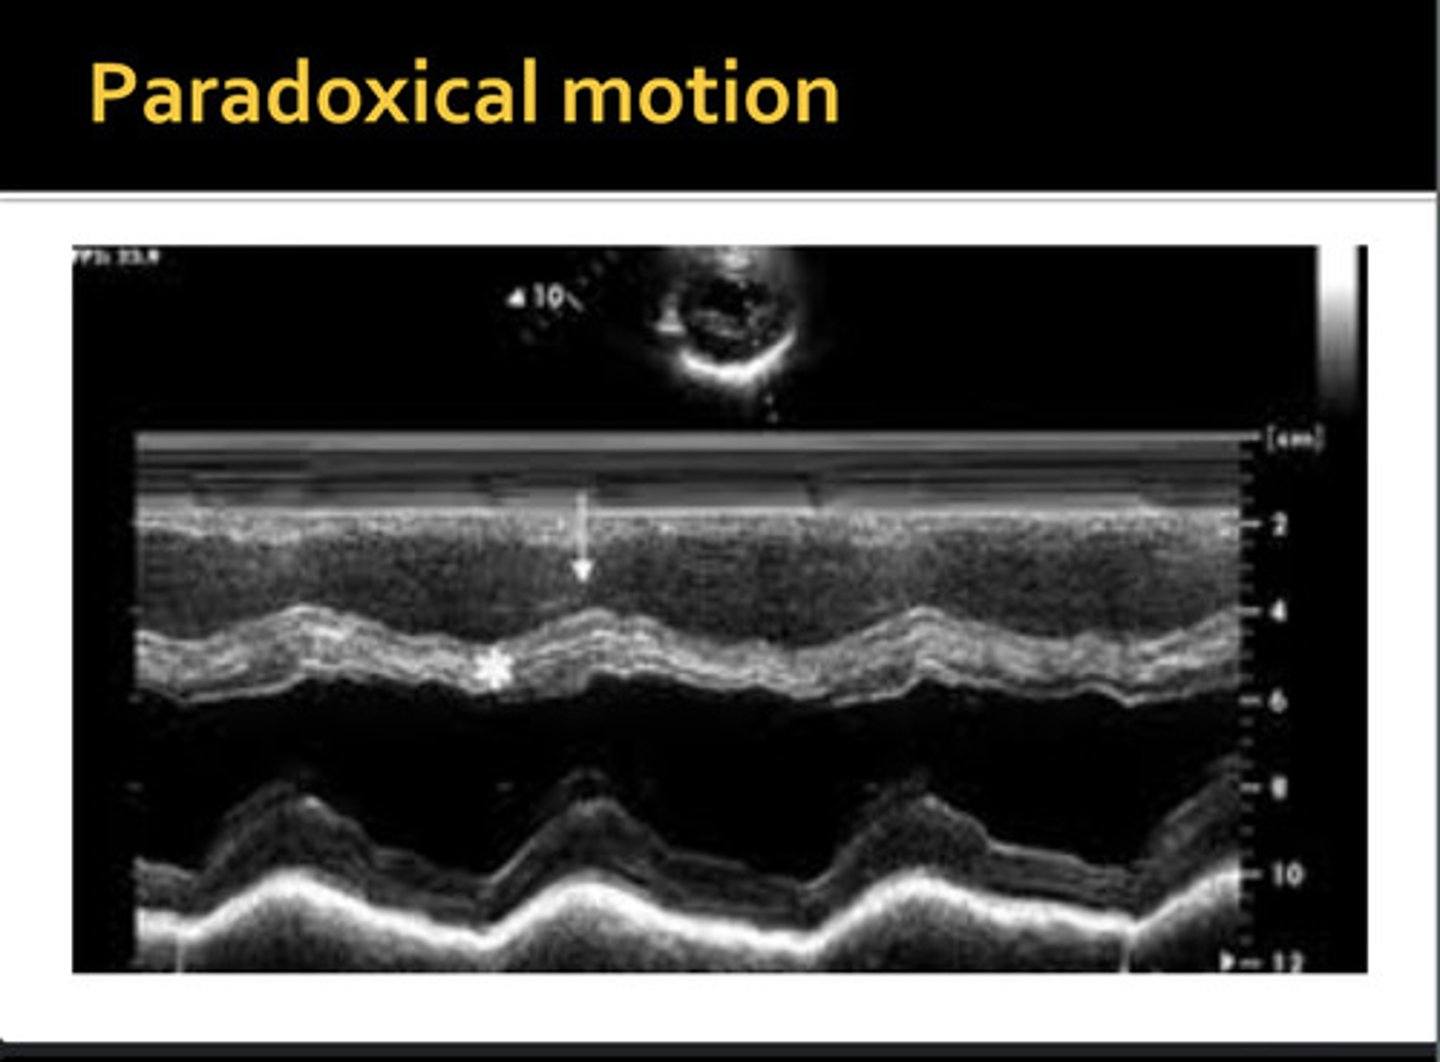

movement away from the opposite wall during systole; IVS moves away from free wall and posterior inferior away from pericardium

paradoxical wall motion